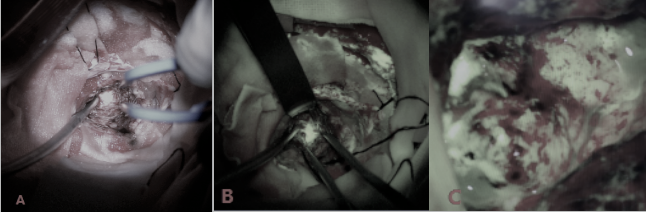

(术中超声定位)

(术中荧光判断肿瘤边界)

(术中唤醒麻醉)

如果你还会担心手术不安全,那么我告诉你开颅手术中,患者不仅可以醒着,而且还有医生在身旁谈话聊天,你还会觉得不安全吗?